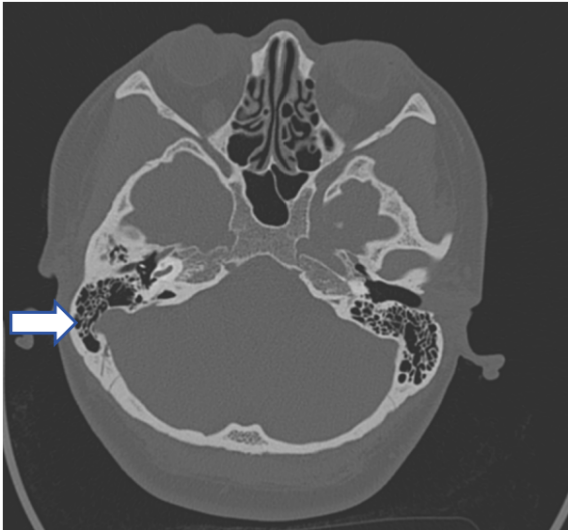

CT示:右乙状窦憩室侵入右颞骨及乳突气房

初步诊断

血管性耳鸣、乙状窦憩室